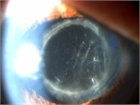

1. 感染性眼内炎とは病原微生物の眼内感染により生じる虹彩毛様体炎、網脈絡膜炎の総称である。

1. 急性術後細菌性眼内炎に対しては、早期に硝子体手術および強力な抗炎症療法(ステロイド薬の全身・局所投与)を行う。